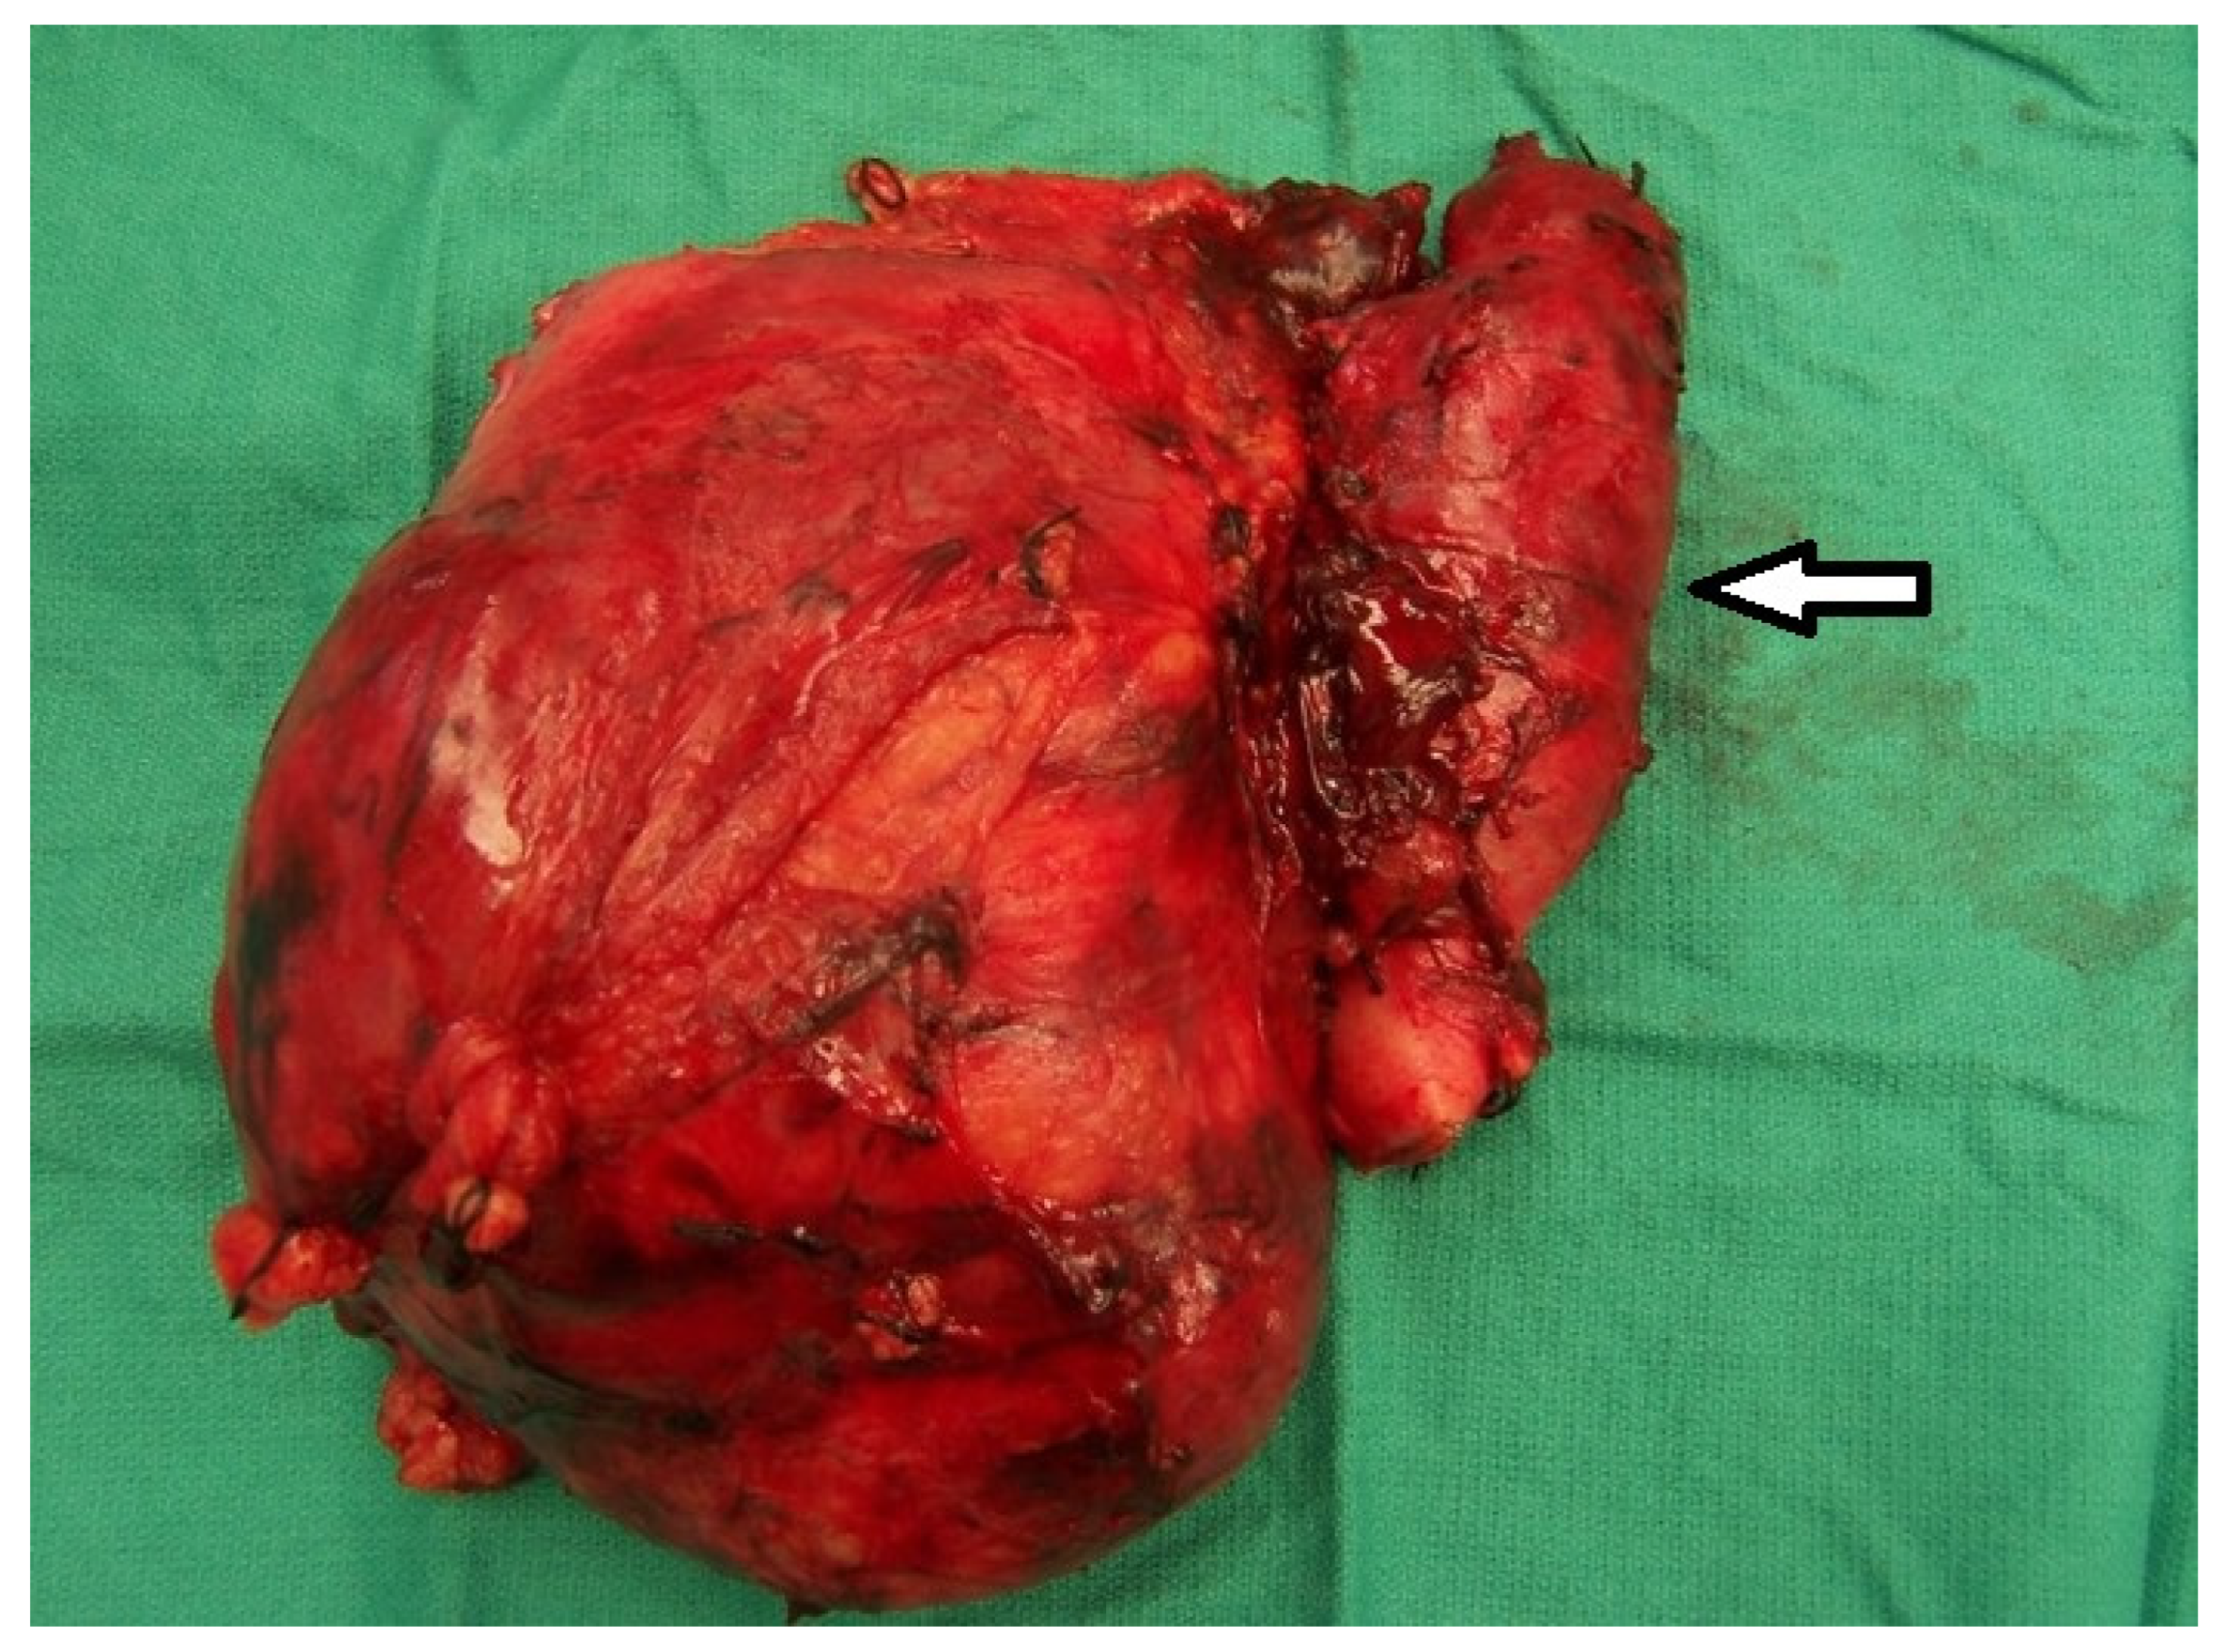

1. Introduction

2.2. Radical Nephrectomy and Tumor Thrombectomy

2.2.3. Level III and Level IV TT